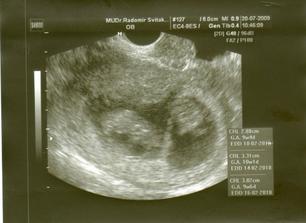

31.7. K.O - riziková poradna OBI pro vícečetné těhu. Jinka předána do péče svého gynekologa.